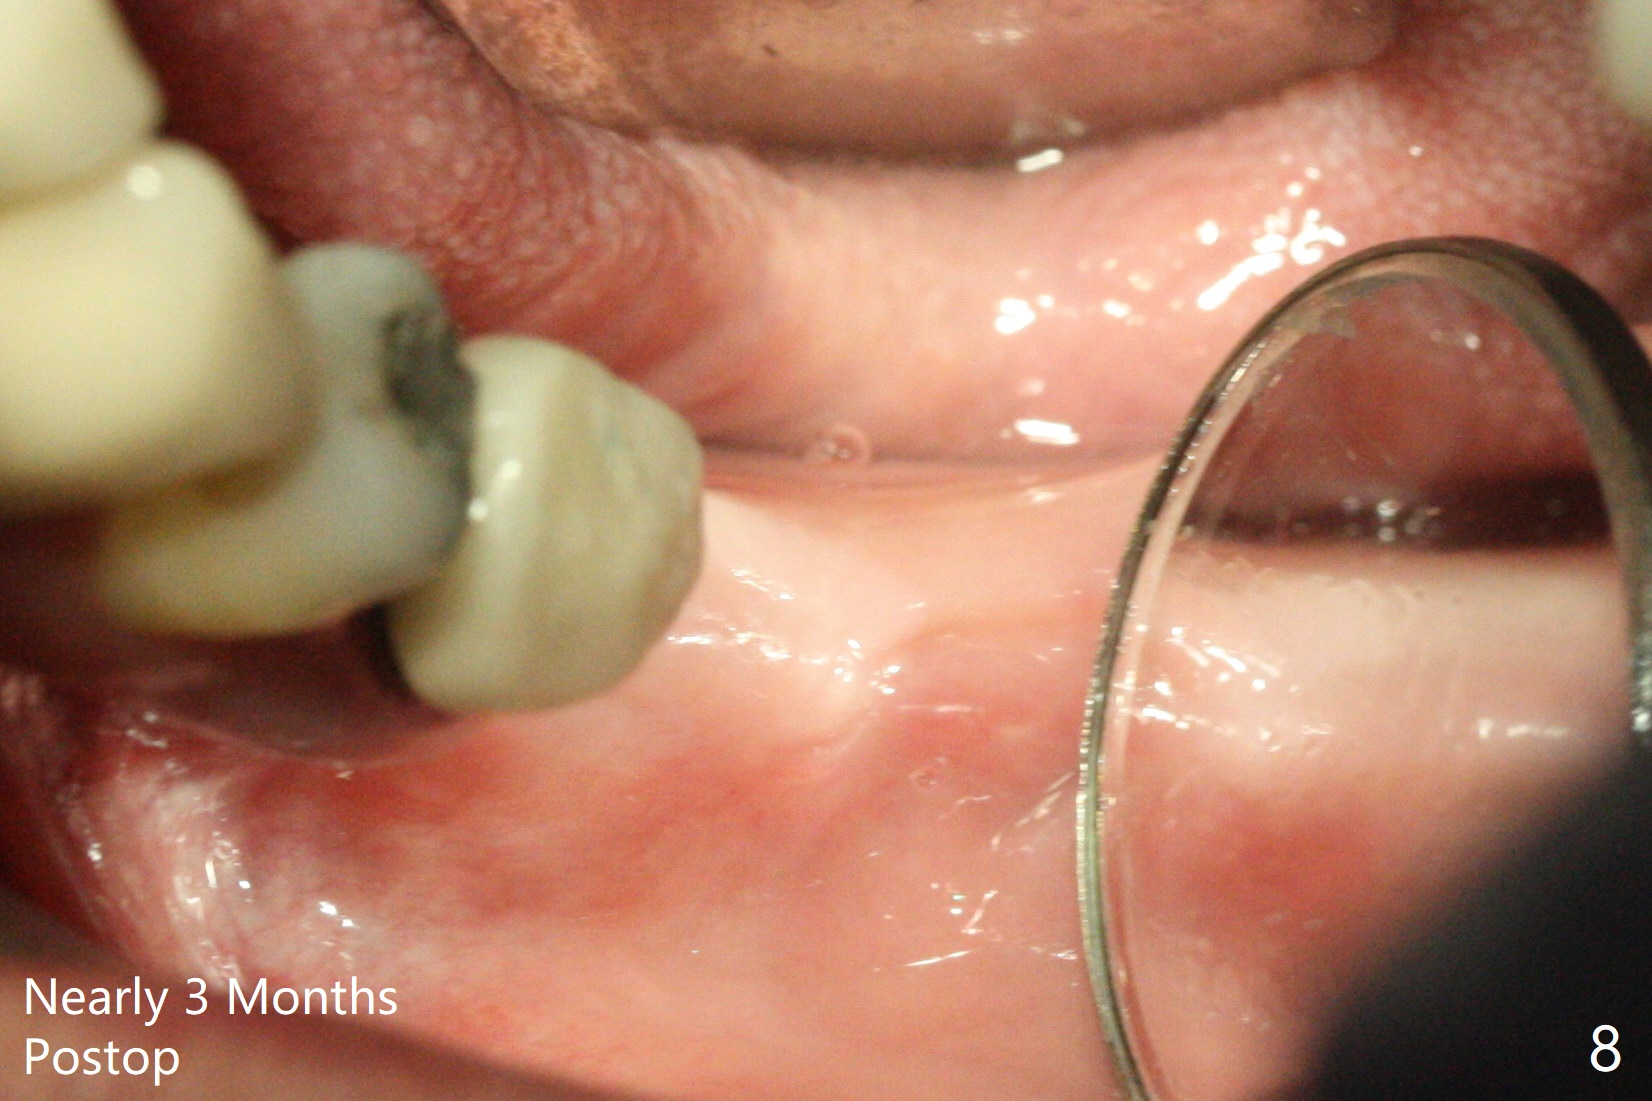

The ridge at #19 looks wider than that at #18 nearly 3 months postop (Fig.8).